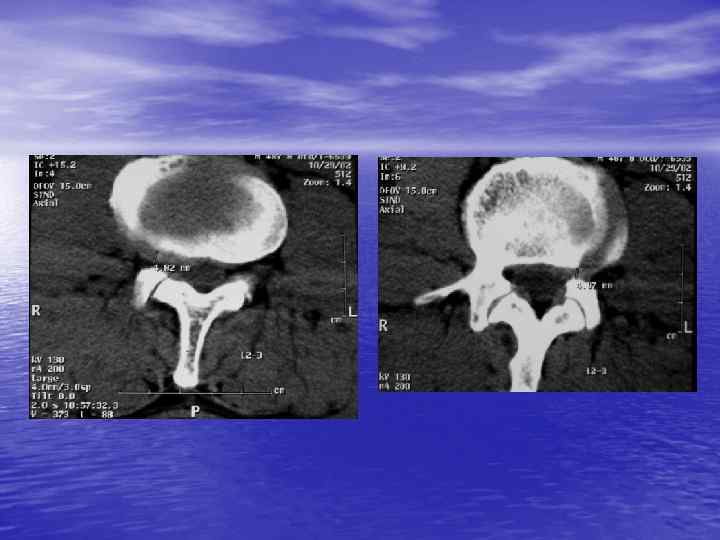

Структурный анализ Оценка основных макроскопических признаков: - положение - форма - размеры - характер контуров и структур патологически измененных участков

Структурный анализ

Денситометрический анализ Определение основных видов патологических образований: - обызвествленных - мягкотканных - жидкостных - жиросодержащих - воздухсодержащих